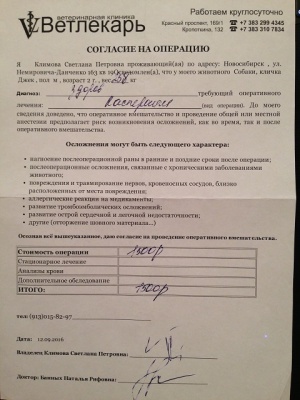

– кастрация по проекту «Все в моих руках», клиника Ветлекарь, хирург Тетерин Олег Анатольевич (чек 2, товарный чек 2, согласие на операцию – документ 2, рекомендации – документ 2-2) – 1500 руб.;

– кастрация по проекту «Все в моих руках», клиника Ветлекарь, хирург Тетерин Олег Анатольевич (чек 2, товарный чек 2, согласие на операцию – документ 2, рекомендации – документ 2-2) – 1500 руб.;

12.09.2016, перед началом пиара, проведена кастрация в клинике Ветлекарь, по льготной программе Все в моих руках. Кастрировал Джека сам Олег Анатольевич Тетерин.

12.09.2016, перед началом пиара, проведена кастрация в клинике Ветлекарь, по льготной программе Все в моих руках. Кастрировал Джека сам Олег Анатольевич Тетерин.